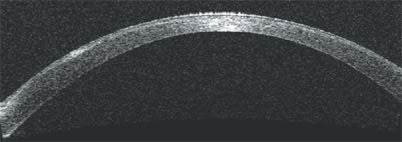

The high-resolution corneal scan provides anatomic validation of the thinning indicated by the pachymetry map and the anterior-segment scan.

A high-resolution corneal scan and analysis confirms a residual stromal bed thickness of 228 μm, a contraindication for a LASIK enhancement procedure.